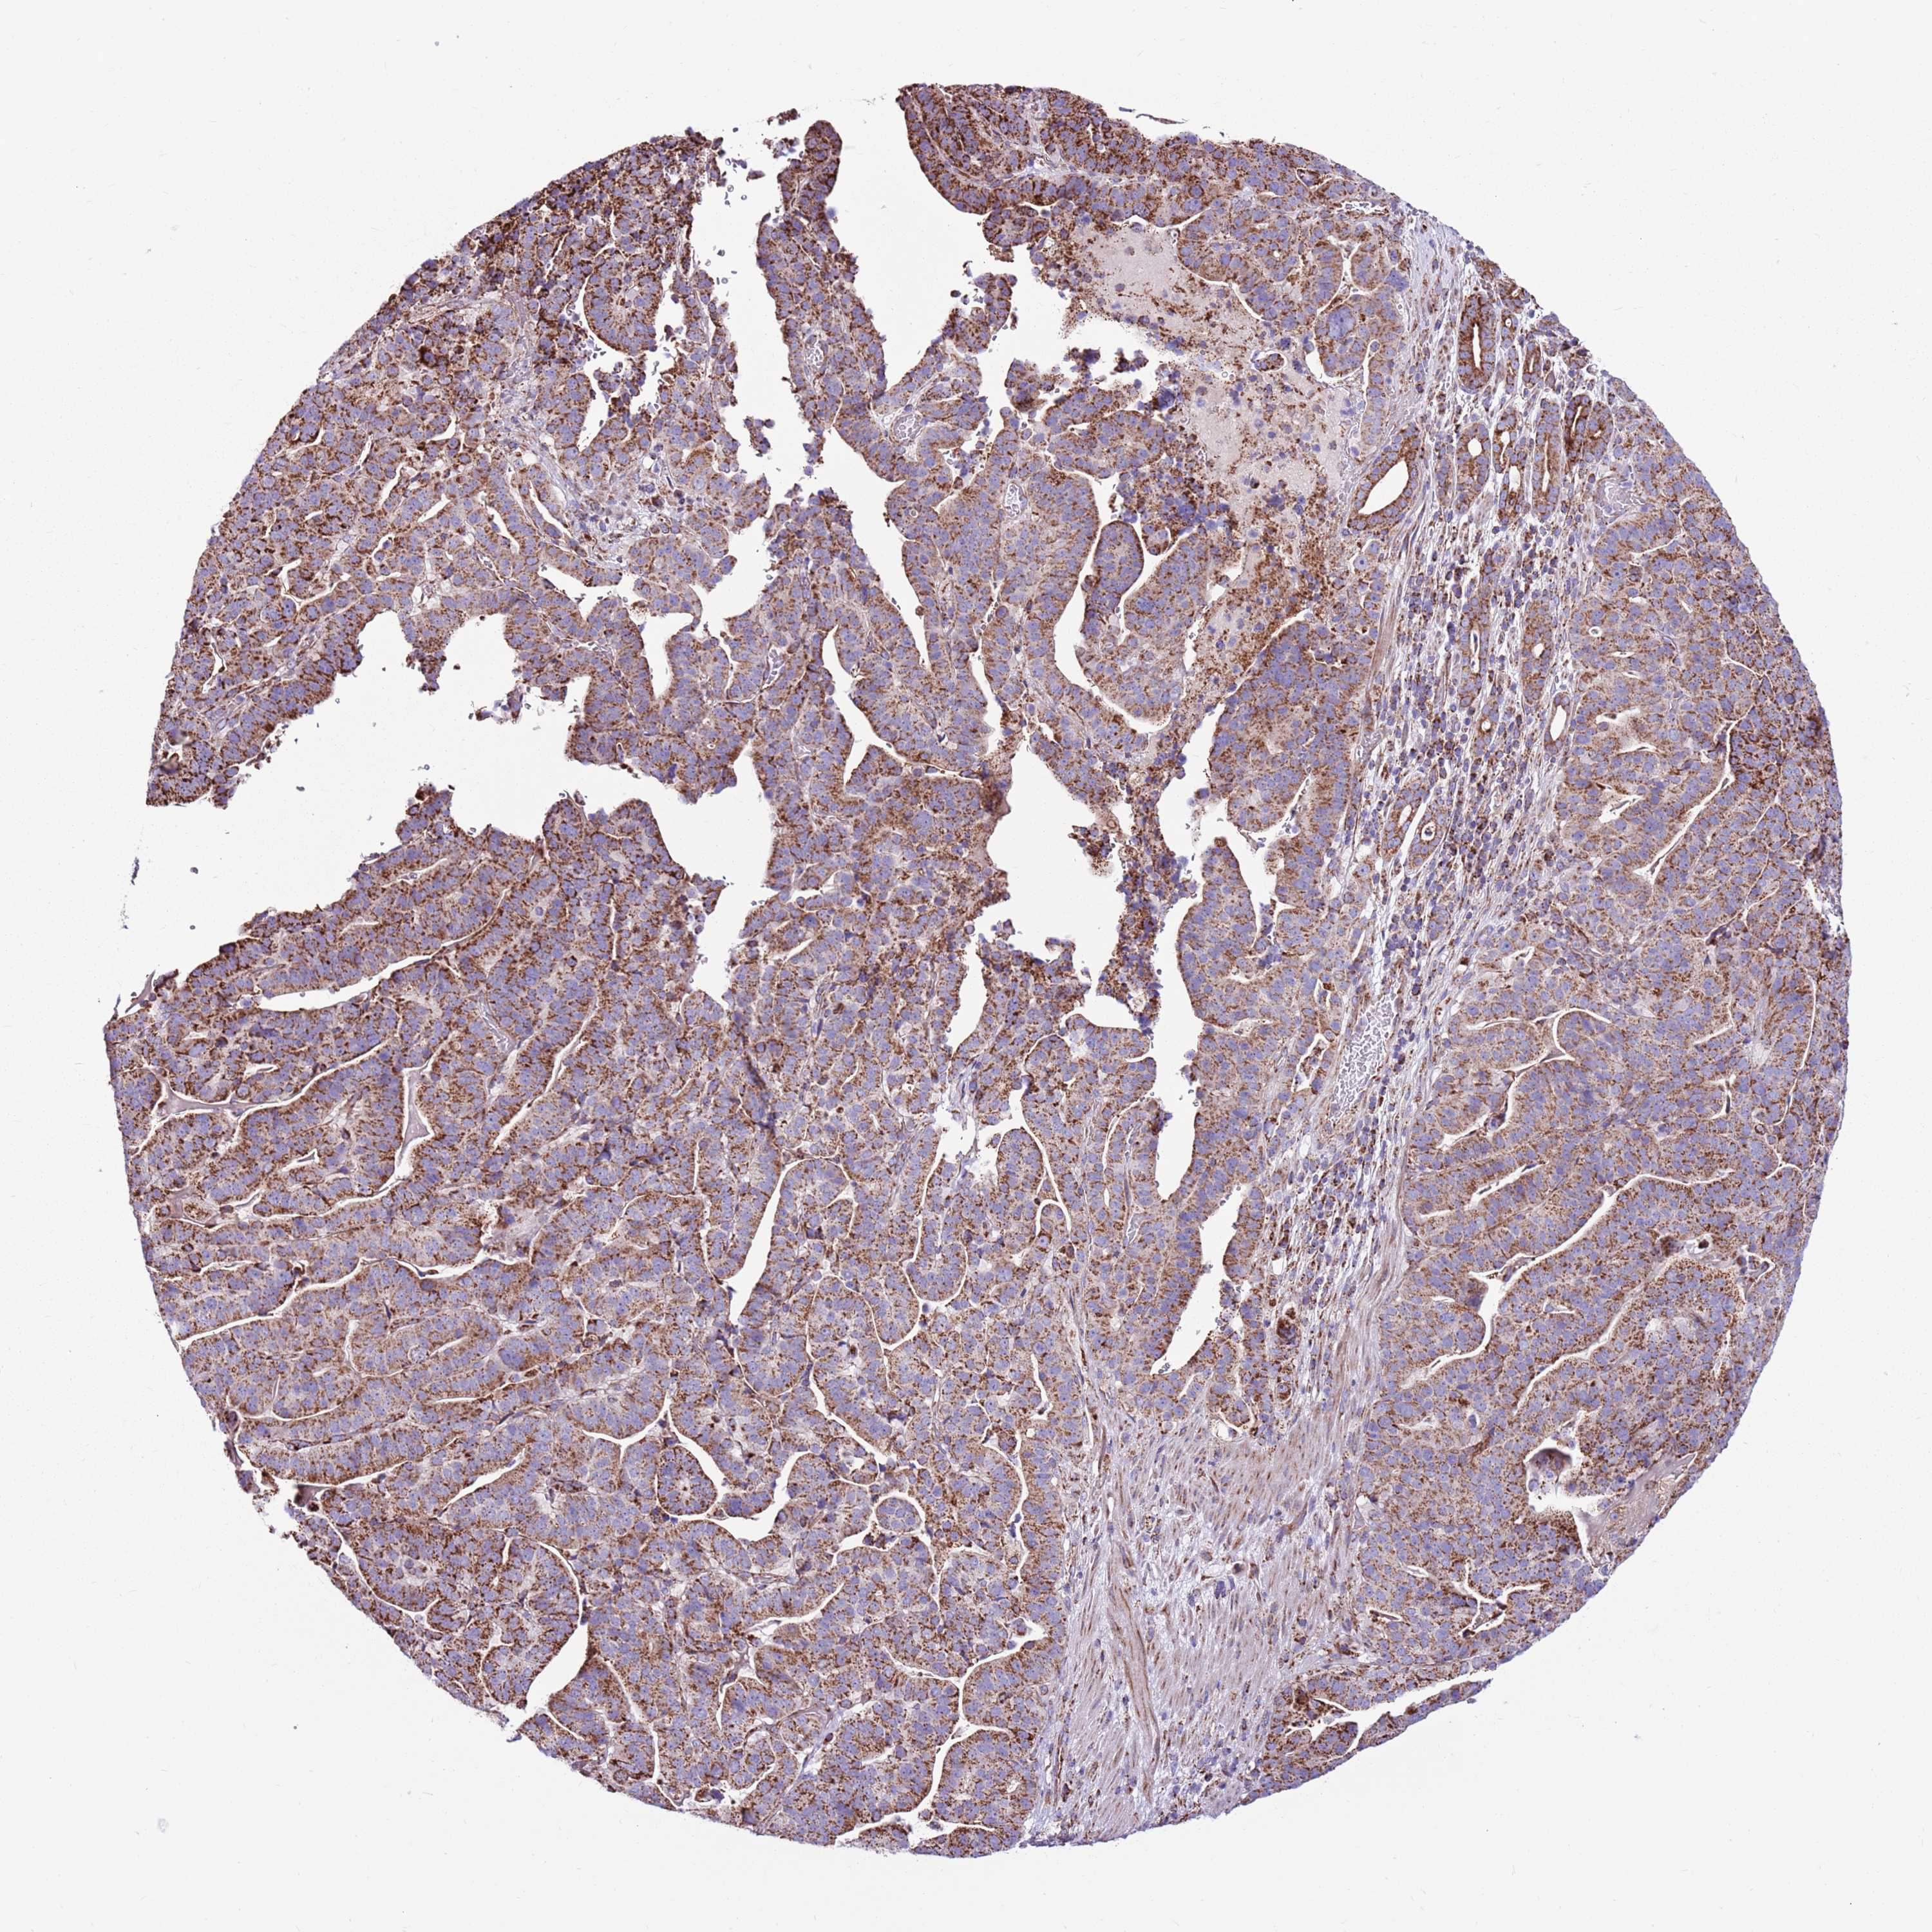

STOMACH CANCER - Protein expressioni

A mouse-over function shows sample information and annotation data. Click on an image to view it in a full screen mode. Samples can be filtered based on level of antibody staining by selecting one or several of the following categories: high, medium, low and not detected. The assay and annotation is described here.

Note that samples used for immunohistochemistry by the Human Protein Atlas do not correspond to samples in the TCGA dataset.

Antibody stainingi

Antibody staining in the annotated cell types in the current human tissue is reported as not detected, low, medium, or high, based on conventional immunohistochemistry profiling in selected tissues. This score is based on the combination of the staining intensity and fraction of stained cells.

Each image is clickable and will lead to virtual microscopy that enables deeper exploration of all samples and also displays staining intensity scores, fraction scores and subcellular localization as well as patient and tissue information for each sample.

Antibody HPA041062

Antibody HPA045473

Staining

High

Medium

Low

Not detected

Intensity

Strong

Moderate

Weak

Negative

Quantity

>75%

75%-25%

<25%

None

Location

Nuclear

Cytoplasmic/membranous

Cytoplasmic/membranous,nuclear

Adenocarcinoma, NOS